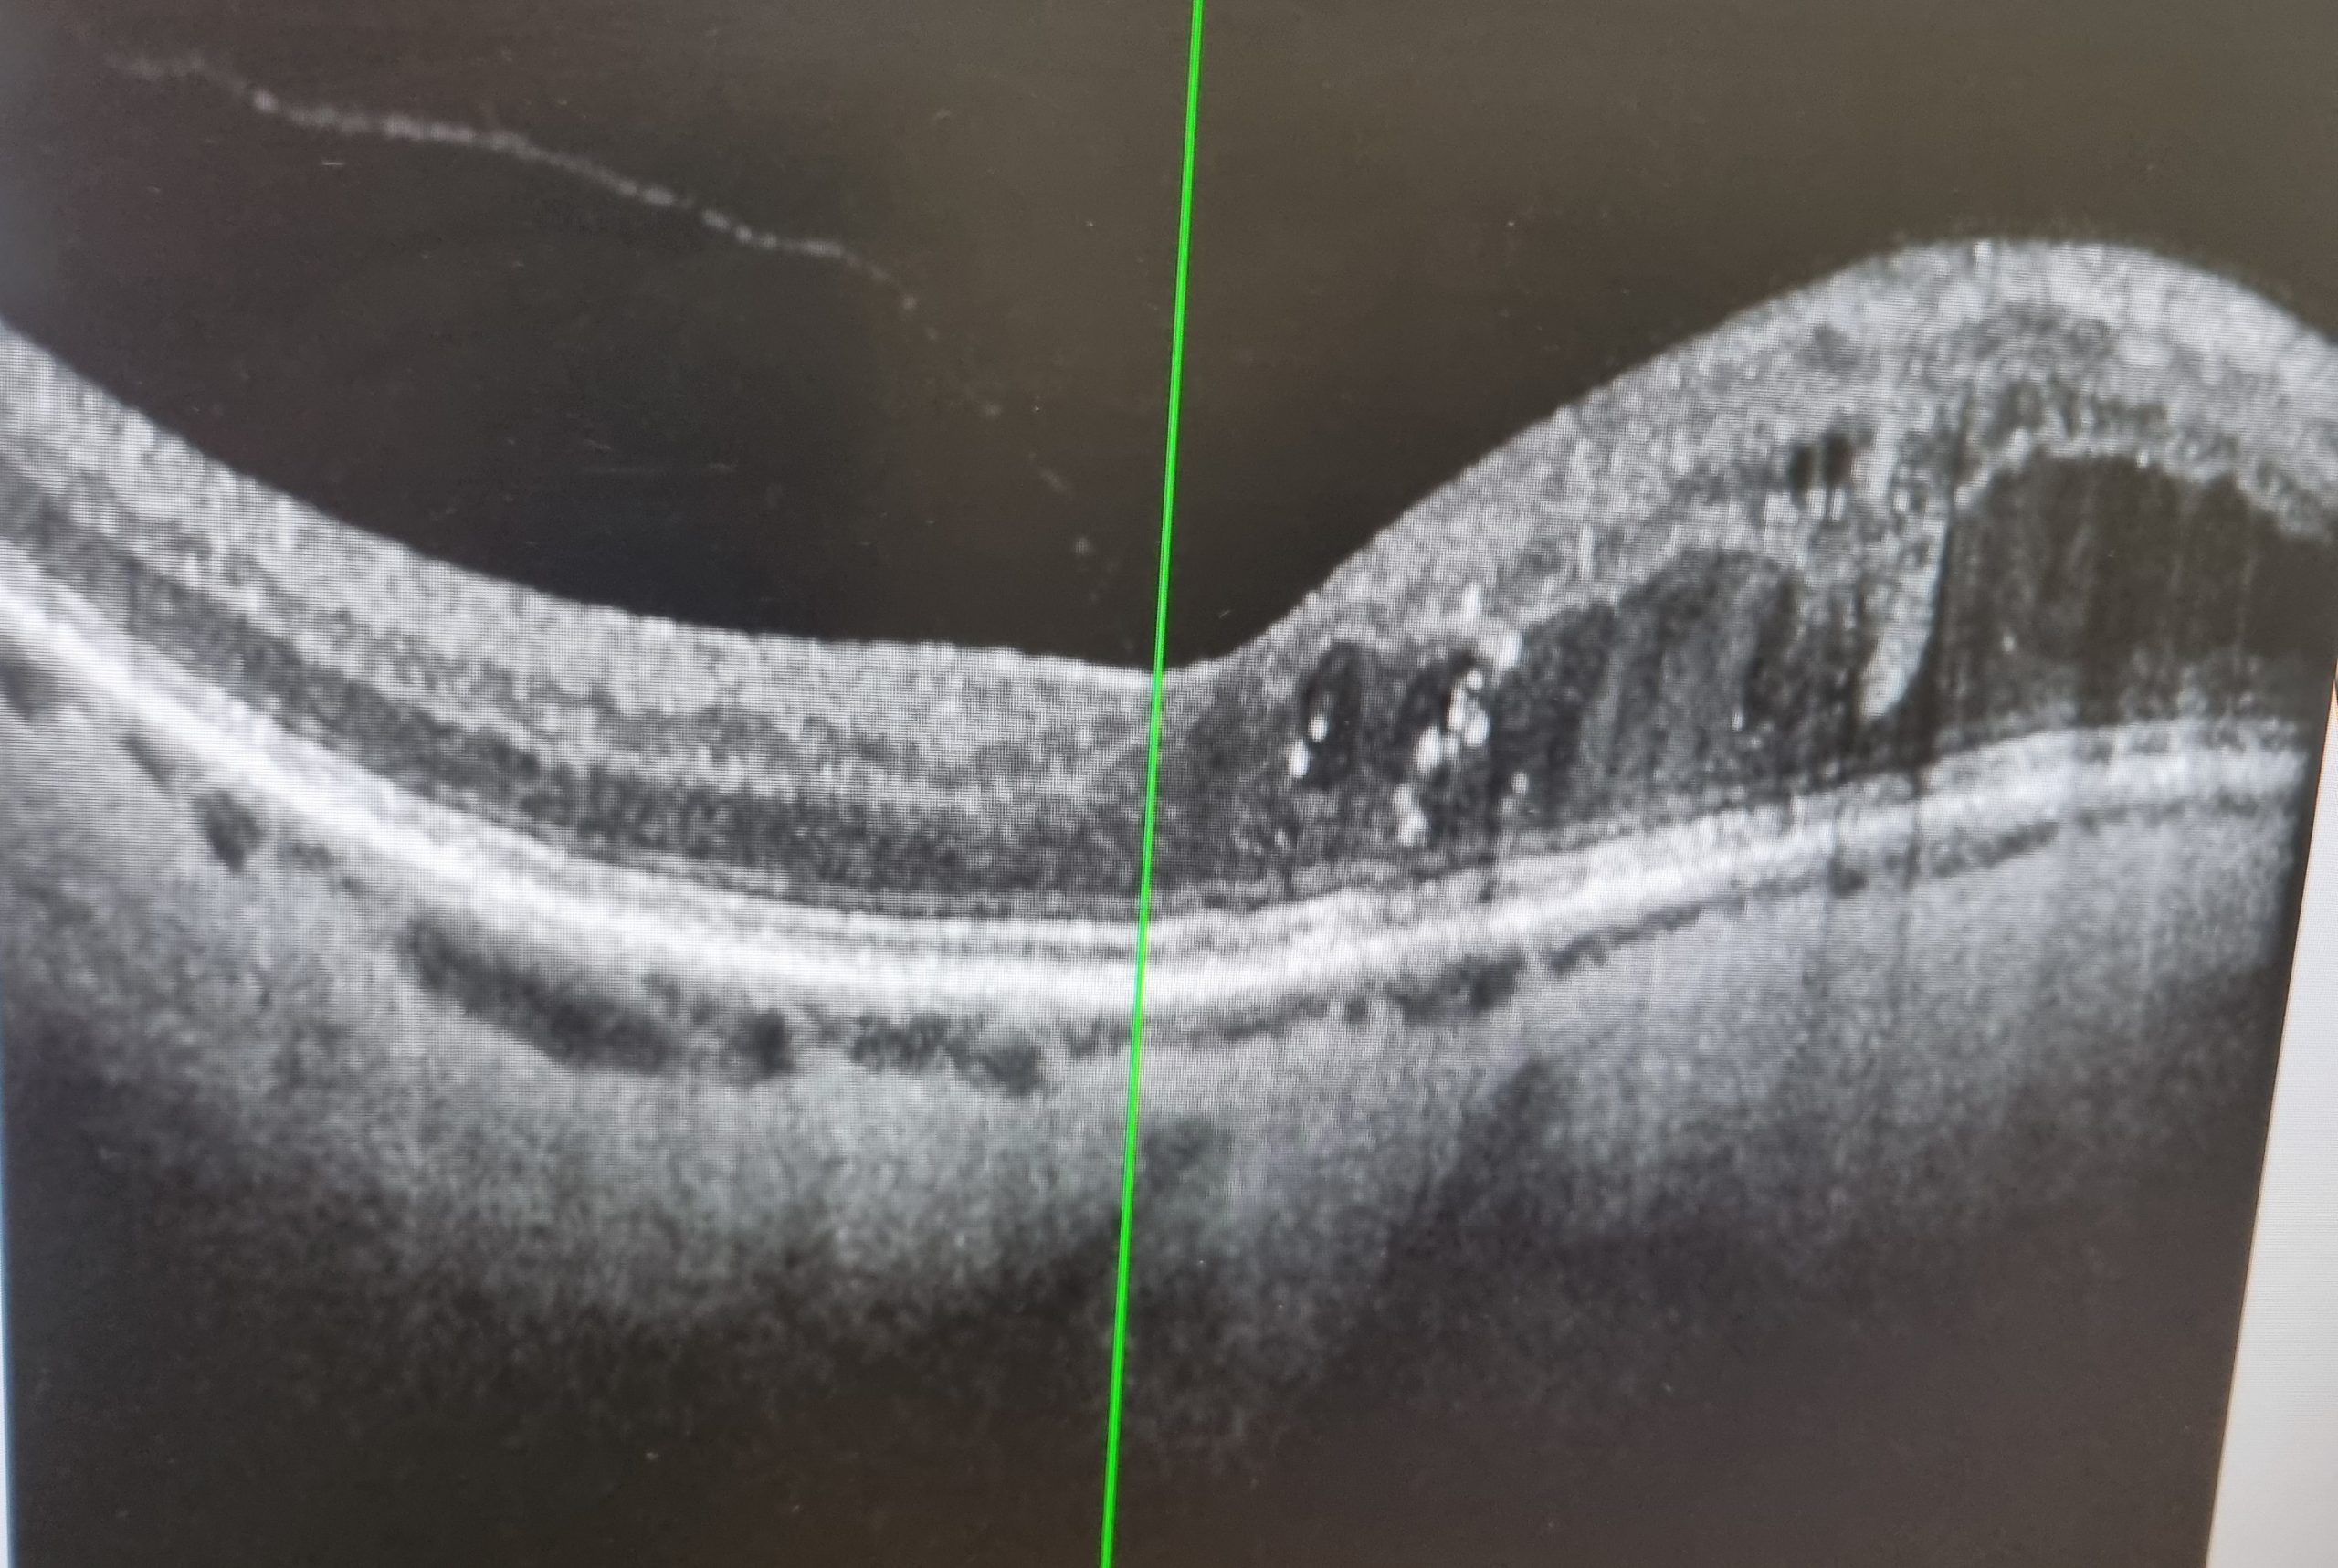

So into the car and off to the Macula Centre in Bradford. Fortunately the traffic wasn’t too bad so we arrived in good time. After checking in at reception it was a case of going through the various stations. First up, an eye test. The usual rows of letters of decreasing size. I managed the bottom row with my right eye but had to admit it was a bit blurry with the left, just about doable but probably not a good test as I could remeber the letter sequence! In the same room i had my eyeball pressures measured before pupil dilating drops were administered.

The top image is my oedema on my previous visit to the clinic shown as a heat map. Green is normal retinal thickness, yellow to red for increasing thickness and the white are being the maximum thickness. The numbers in the grid give an average thickness in each section. Note the retinal thickness is measured in micrometers, there are thousand micrometer in every millimeter. This gives some idea of how thin and delicate the retina is.

The middle image shows the oedema on my recent visit. Happily it has shrunk considerably and hopefully this will continue until it disappears.

The lower image shows the change between the two.

My thanks to Ms Shetty, the opthalmologist for taking the screen shots for me.

The opthalmologist was very pleased with progress since my last visit and treatment. The expectation s that the oedema will continue to shrink as the steroid implant continues to do its job. The implant lasts 3 – 6 months so plenty of time left yet. So no further treament required at this stage.

I’ll have another appointment in around 8 weeks time. As explained, the oedema may come back at some point so there will have to be regular monitoring. Some patients require multiple rounds of treatment. The important thing is to keep good control of my diabetes as this will greatly reduce the chance of recurrence.